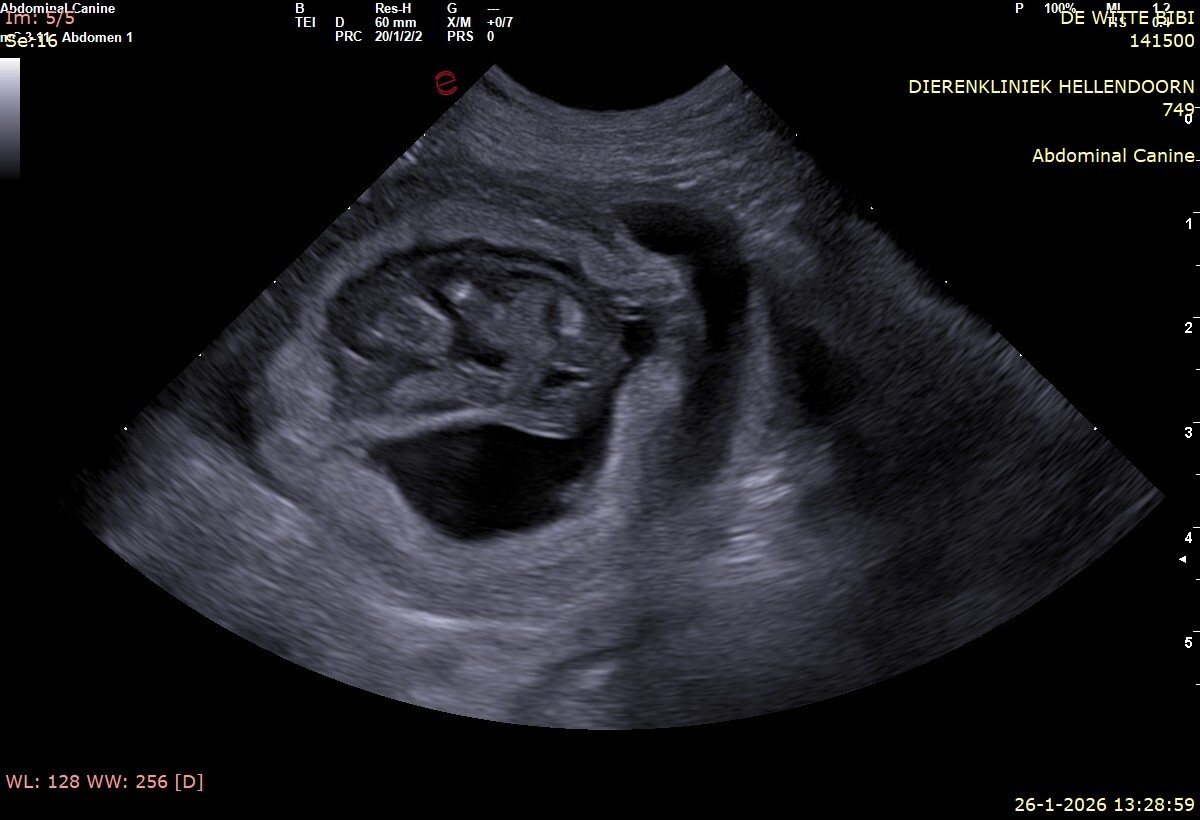

Op 24 Februari zijn er Bouvierpups geboren van Bibi en Ozzy (Aristocrat Astronaut) Het zijn maar liefst 6 teefjes en 4 reutjes geworden. Beide ouderdieren zijn HD-A, ED vrij en ECVO vrij getest.

Bibi ⬇